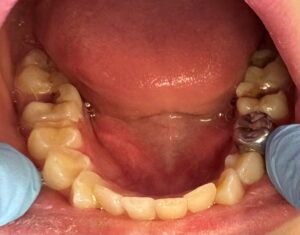

We’re seeing a lot of kids at 5 and 6 years old, and it’s not fillings that we’re doing — it’s crowns and extractions and spacers.

“We’re seeing a lot of kids at 5 and 6 years old,” Robertson says, “and it’s not fillings that we’re doing — it’s crowns and extractions and spacers.”

We’re doing a lot of sedations. We’re doing a lot of general anesthesia appointments. We’re doing a lot of silver diamine fluoride (SDF) on those individuals because we’re not going to see them under general anesthesia or sedation until they’re at least 2 years old and 25 pounds. With SDF, we’ve been able to push it to 3 years old and 30 pounds. Seeing a child closer to 3 ensures all the baby teeth have come in and decreases the chances of additional sedations in the future.